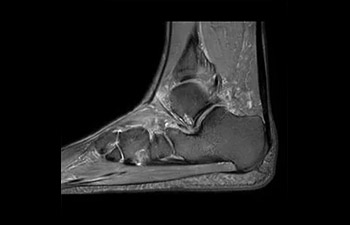

com Compressed SENSE

Leia sobre as experiências do Kantonsspital Winterthur (Suíça), que experimentou o Compressed SENSE como uma forma simples, mas poderosa de acelerar as varreduras de IRM para diferentes tipos de contrastes e sequências tanto em 2D quanto em 3D.